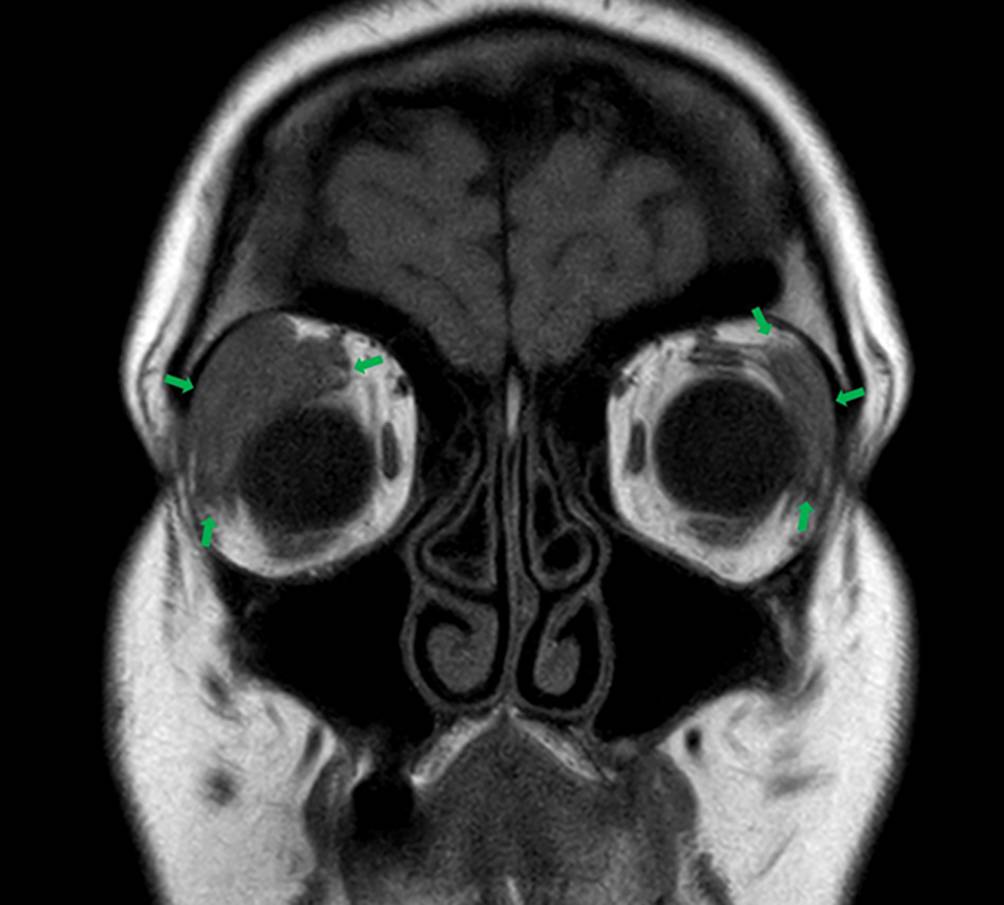

Abb. 2

Magnetresonanztomographie (koronare Schnittebene) mit Darstellung der vergrößerten Glandulae lacrimales beidseitig (grüne Pfeile)

Die Diagnostik wurde um eine Magnetresonanztomographie des Schädels mit Dünnschichtaufnahmen der Orbitae und Nasennebenhöhlen ergänzt. Hier fanden sich signalarme, unscharf begrenzte Schwellungen der Glandulae lacrimales beidseits (Abb. 2). Eine Serologie auf Borrelien, Lues und neurotrophe Viren zeigte keine aktiven Infektionen, aber Serumnarben für Herpes-simplex-Virus (HSV) und Varizella-Zoster-Virus (VZV). Die Titer für das Angiotensin-Converting-Enzym (ACE) und den löslichen Interleukin-2-Rezeptor (sIL-2-R) stellten sich normwertig dar.